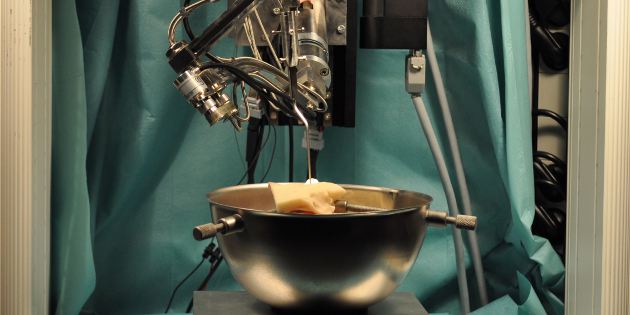

RobOtol®, un robot miniinvasif pour opérer l’oreille moyenne et interne